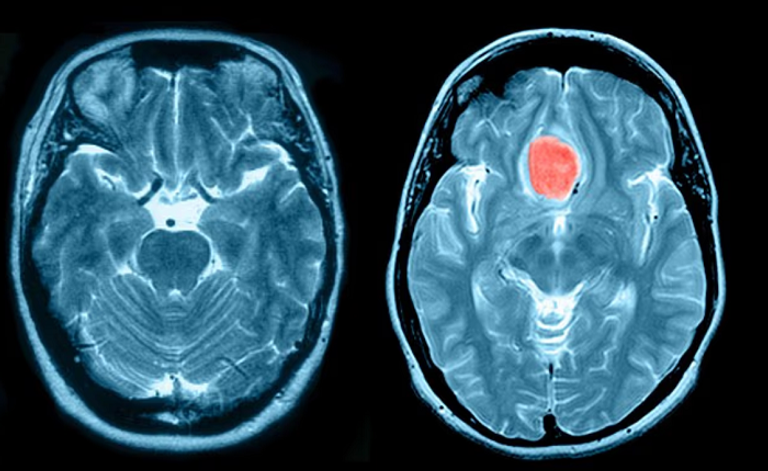

كشفت دراسة علمية حديثة أن النساء اللاتي يستخدمن حقنة منع الحمل الشهيرة "ديبو بروفيرا"، معرضات لخطر الإصابة بالورم السحائي.

وتعد هذه الدراسة الثالثة خلال عام واحد التي تربط بشكل مباشر بين استخدام مادة "ميدروكسي بروجستيرون أسيتات" المكون الفعال في ديبو بروفيرا، وزيادة خطر الإصابة بورم السحايا، وهو أكثر أنواع أورام الدماغ شيوعا.. وفي إنجلترا وحدها، يُصرف نحو 10 آلاف وصفة طبية شهريا لهذا العقار.

رغم أن ورم السحايا عادة ما يكون حميدا (غير سرطاني)، إلا أنه قد يؤدي إلى أعراض شديدة مثل الصداع المزمن، اضطرابات الرؤية، فقدان السمع، ومشاكل في البلع أو الشم، وقد يضغط على الدماغ والأعصاب مسبّبًا مضاعفات قد تصل إلى الوفاة إذا لم يُعالج.

ويُشخص بين 2000 إلى 3000 حالة سنويا في المملكة المتحدة، وغالبا ما تصيب النساء أكثر من الرجال.